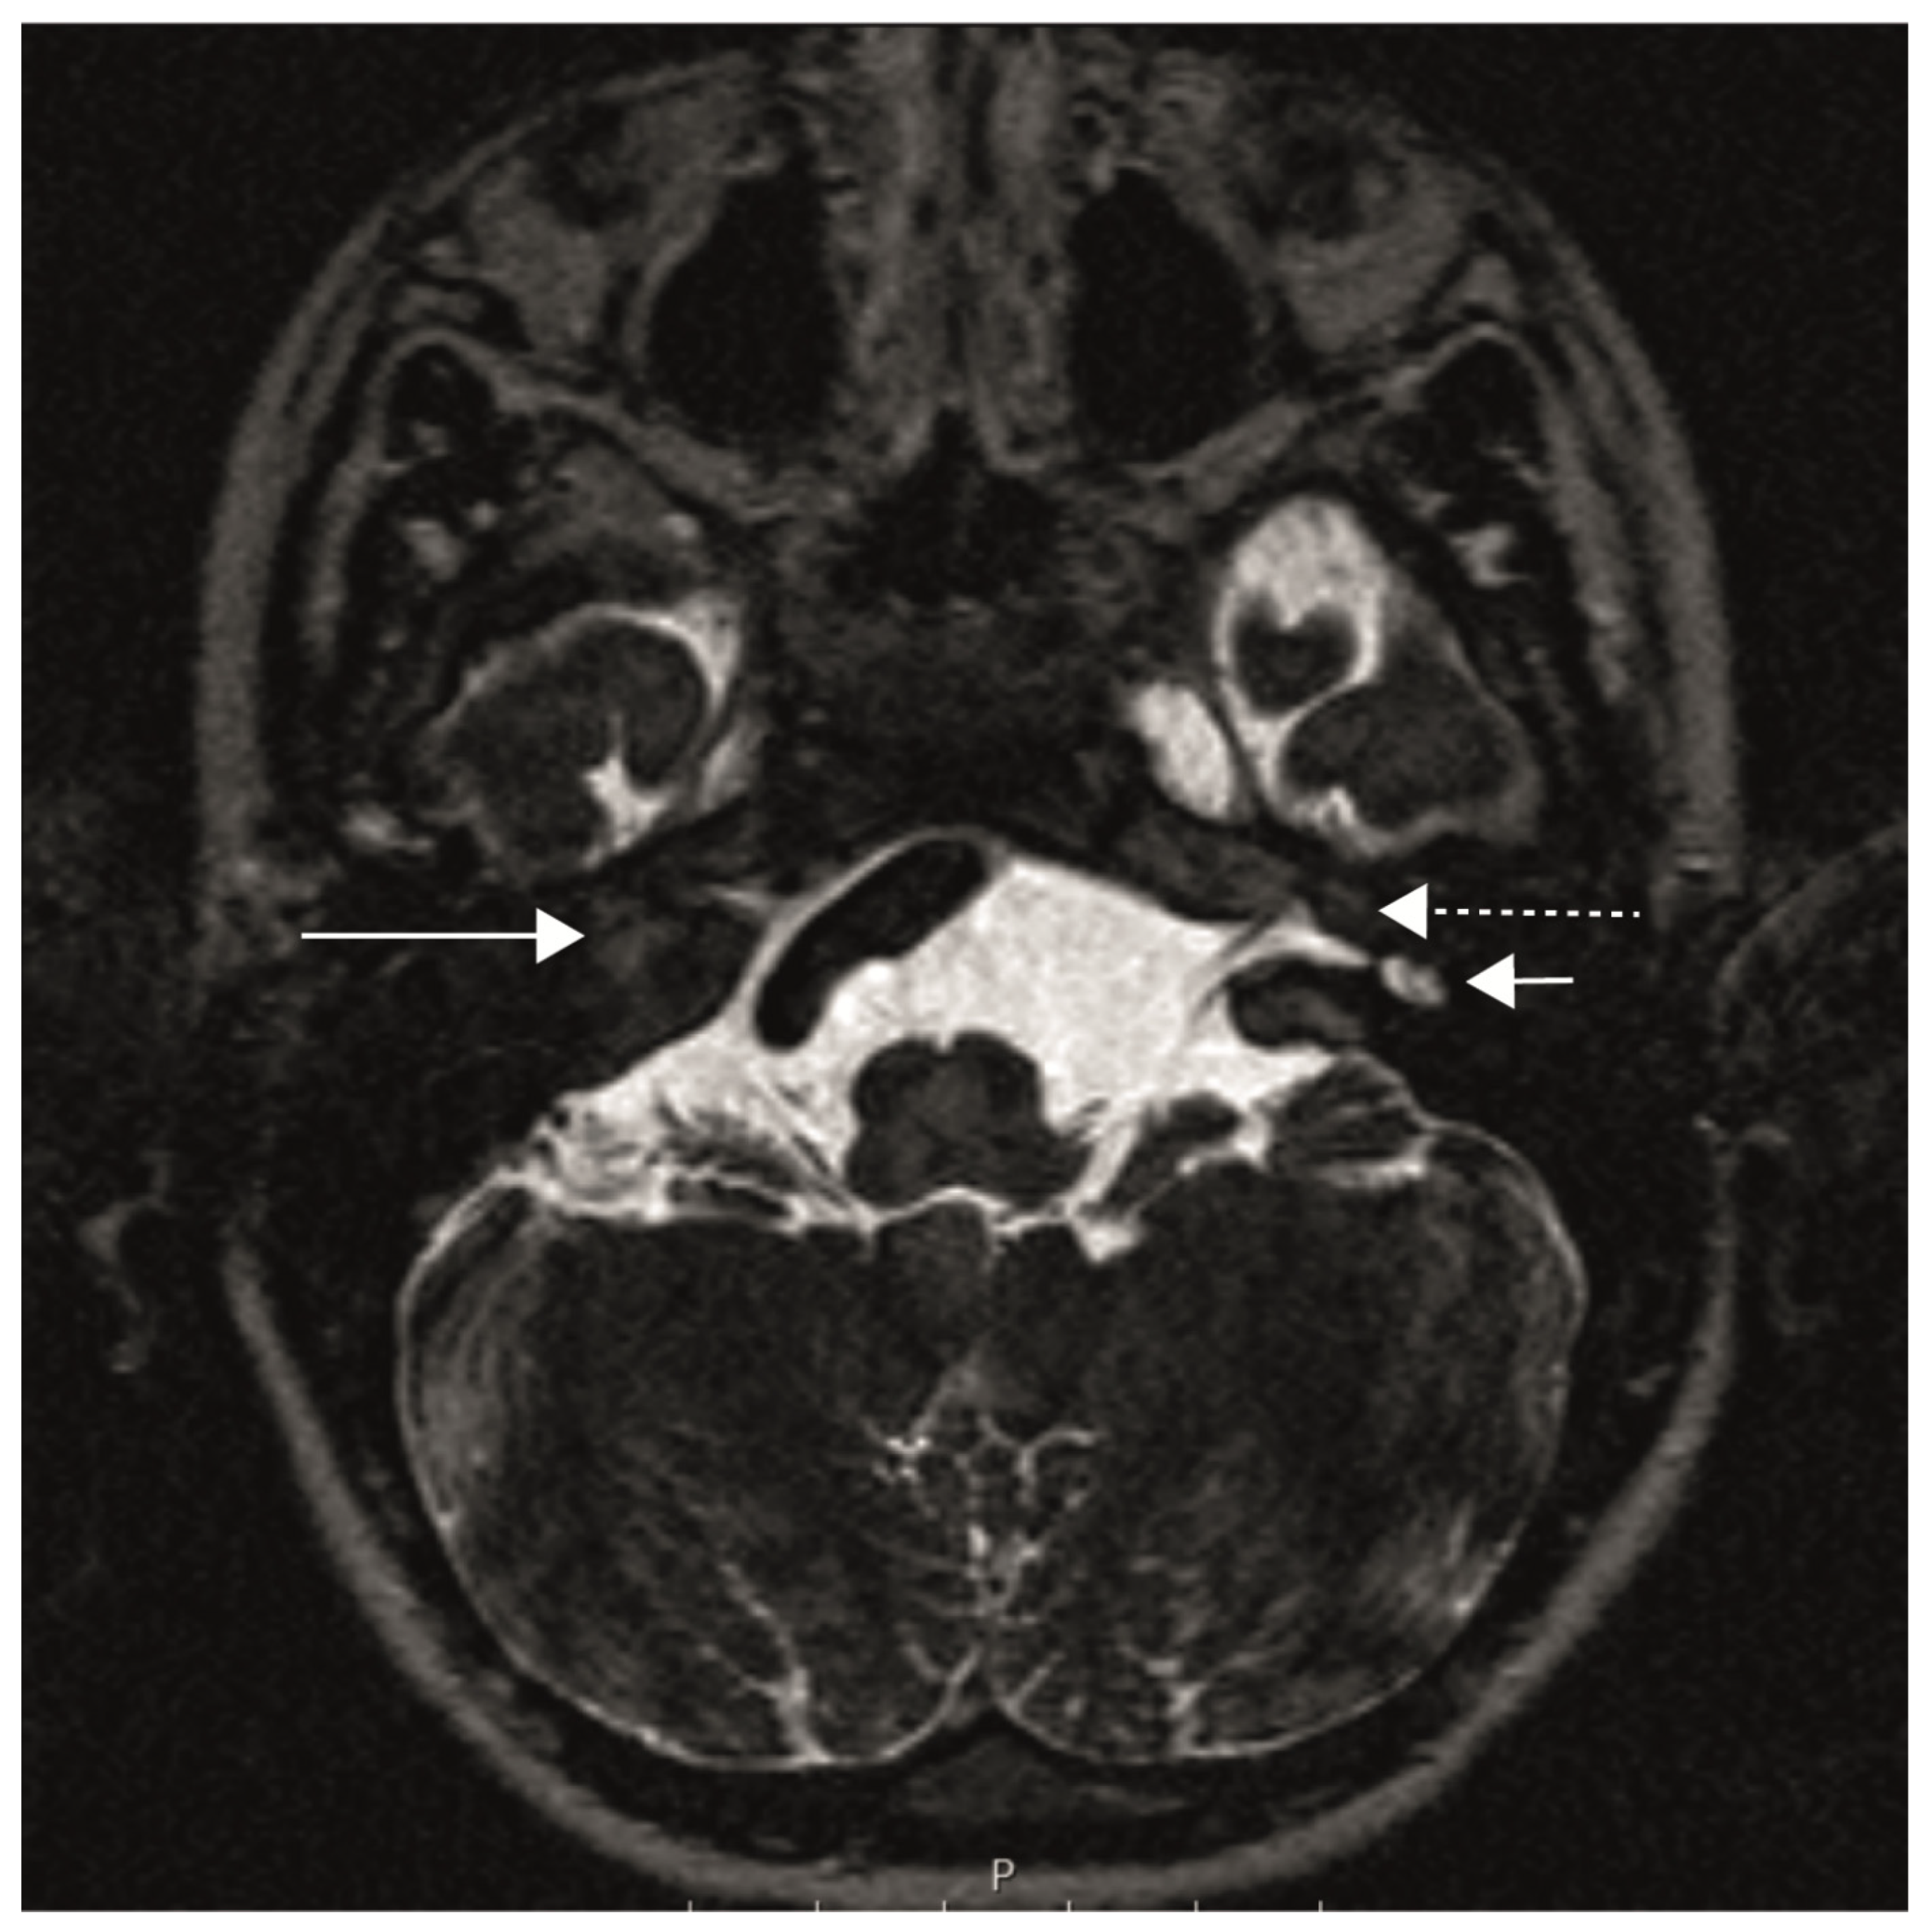

The patient had bilateral cochlear aplasia, which is known to occur in some, but not in all, patients with Bosley–Salih–Alorainy syndrome [8,11]. Figure 1 shows an MRI of the temporal bone with a bilateral cochlear aplasia, an aplasia of the labyrinth on the right and a dysplastic vestibule on the left.

Figure 1.

MRI of the temporal bone (axial plane), CISS sequences (constructive interference in steady state) with a right cochlear aplasia (long solid arrow), aplasia of the right inner ear canal, left cochlear aplasia (long dashed arrow) and dysplastic left vestibule (short arrow).